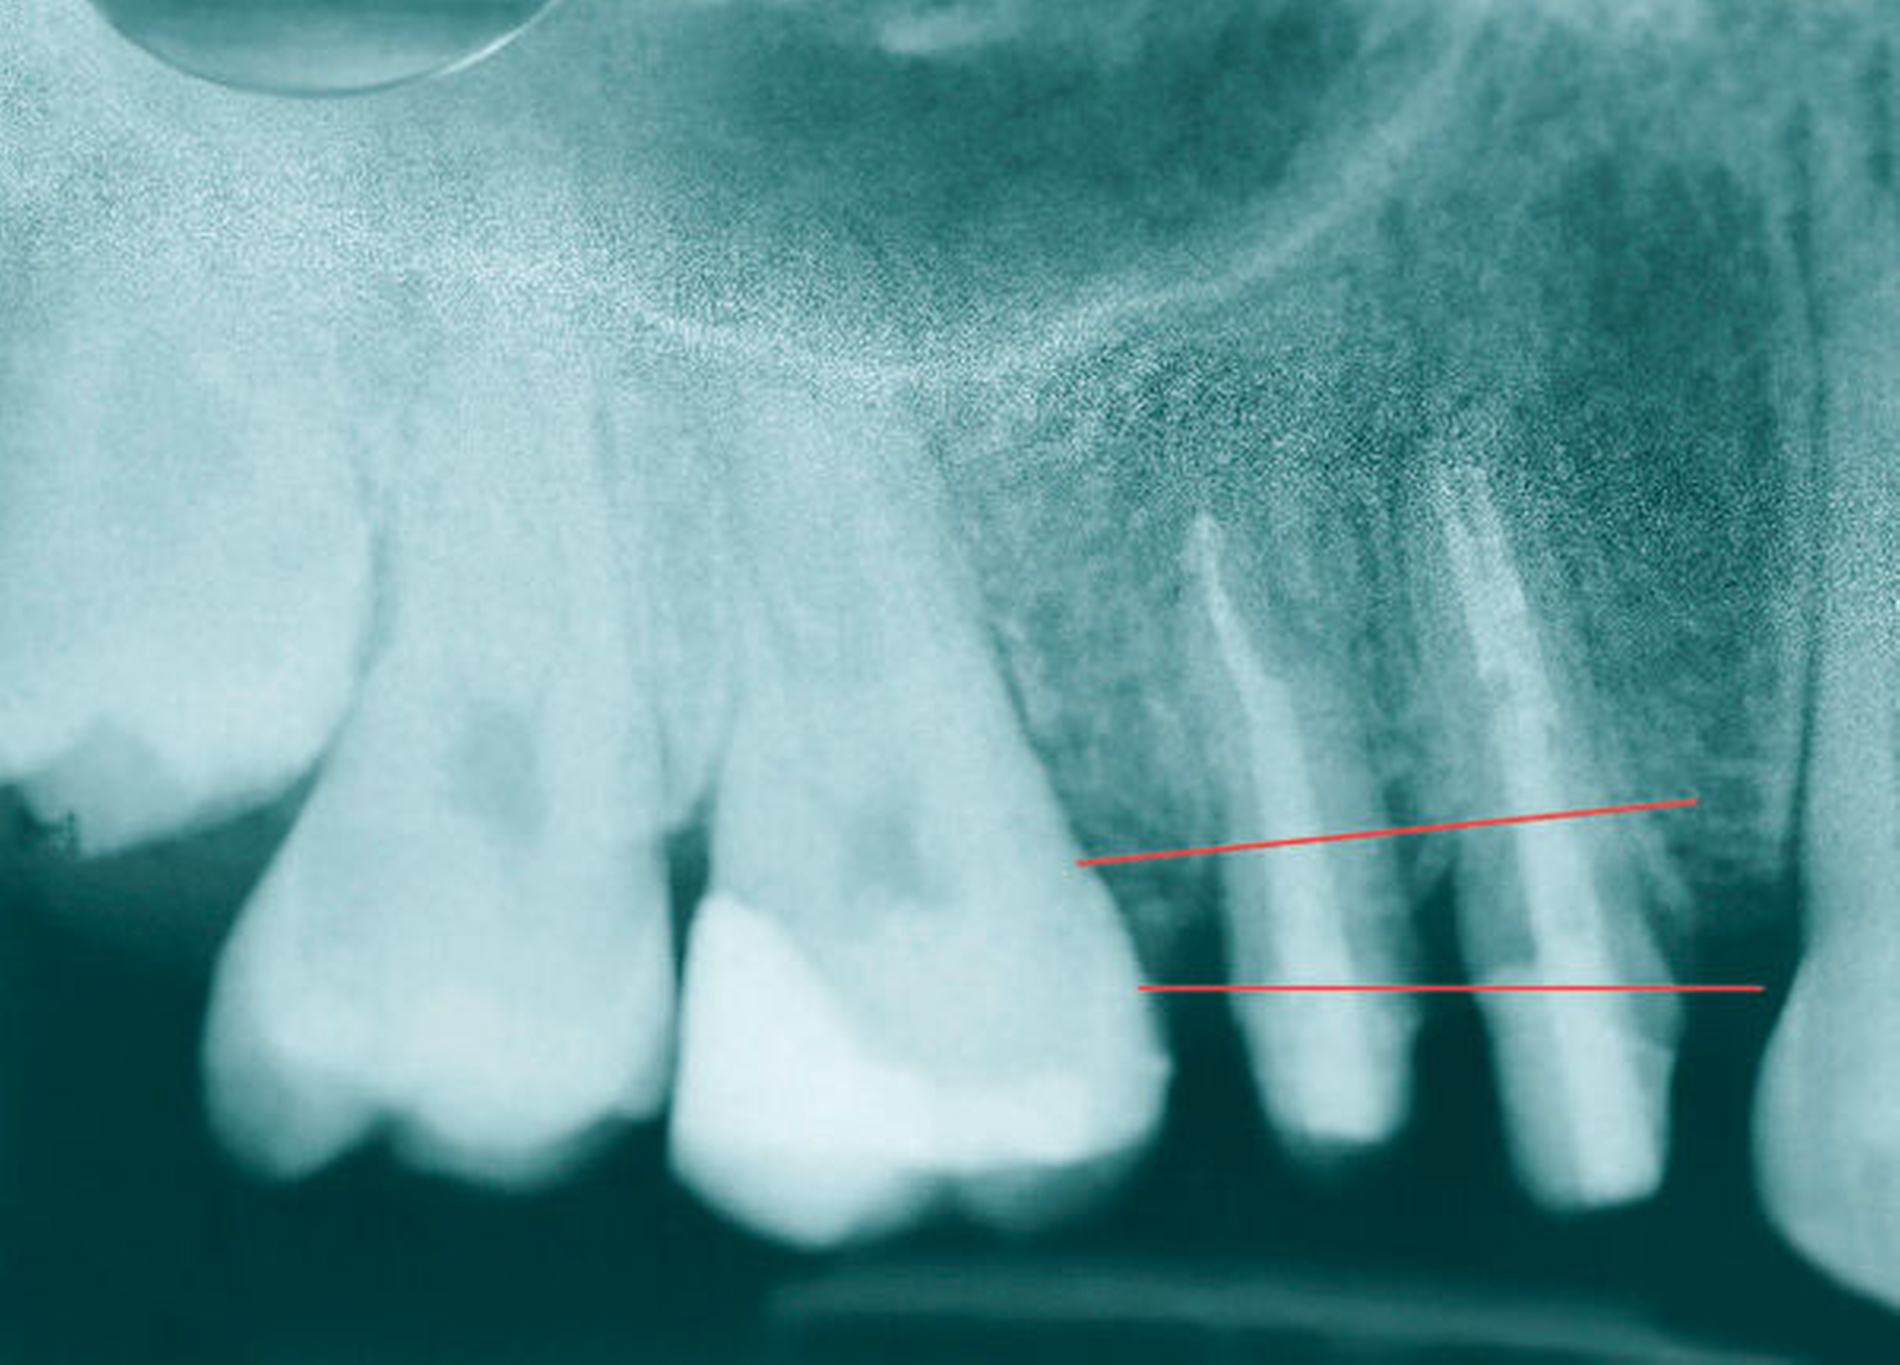

Auch bei scheinbar nicht optimalen Grundvoraussetzungen – wie einem zu erwartenden nicht ganz idealen Kronen-Wurzel-Verhältnis (1:1) – scheint die kieferothopädische Extrusion als Behandlungsoption nicht direkt ausgeschlossen werden zu müssen. Auf dem im Fall gezeigten OPG (Abbildung 9) stellen sich die Zahnwurzeln von 14 und 15 im kontralateralen Vergleich deutlich kürzer dar als die der Zähne 24 und 25. Die elektronische Messlänge bei der Revision der endodontischen Behandlung von Zahn 15 vor Eingliederung des Langzeitprovisoriums betrug lediglich 12 mm. Dennoch wiesen die Zähne 14 und 15 nach der Retentionsphase keine Lockerungsgrade auf, sodass die Autoren in der vermeintlich geringen Wurzellänge keine unbedingte Kontraindikation für das Ziel der Zahnerhaltung sehen. Auch wenn in diesem Fall die unterschiedliche Zahnlänge der Prämolaren im kontralateralen Vergleich klar mit der Extrusion der Zähne 14 und 15 zu erklären ist, stellen kieferorthopädische Bewegungen auch eine mögliche Ursache für die Verkürzung von Zahnwurzeln durch Resorptionen dar.